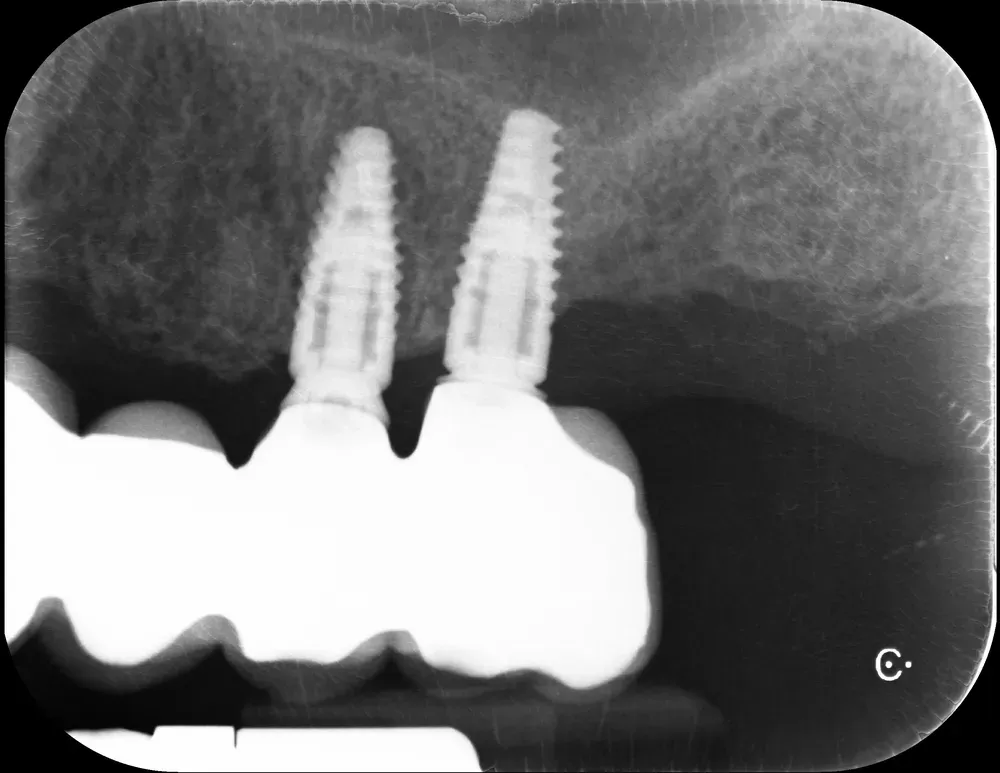

Le immagini sottostanti illustrano la situazione ossea pre-operatoria della cresta alveolare, con una grave atrofia orizzontale, corrispondente alla categoria H3 della Classificazione di Colonia (CCARD).

Secondo la BDIZ EDI, tale grado di atrofia controindica le tecniche espansive.

Personalmente, tuttavia, ritengo che con gli strumenti moderni sia possibile e consigliabile spingersi oltre per includere anche tale livello di atrofia tra le indicazioni. E questo caso lo dimostra.